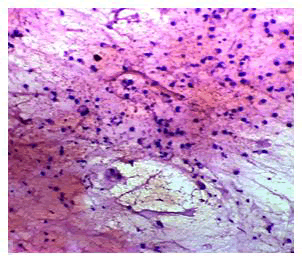

Aspirated smears showed atypical cells, some cells with signet ring cells feature hyperchromatic nuclei in a mucinous background. Impression was given as features are that of malignancy possibly from the metastatic deposit of colon (Figures 1-3).

Figure 1: Cytology smears showing 4x view of atypical cells in a mucinous background.

Figure 2: 40x magnification view showing cells with signet ring cell features.

Figure 3: 10x magnification view showing atypical cells with hyperchromatic nuclei and few with signet ring like features.